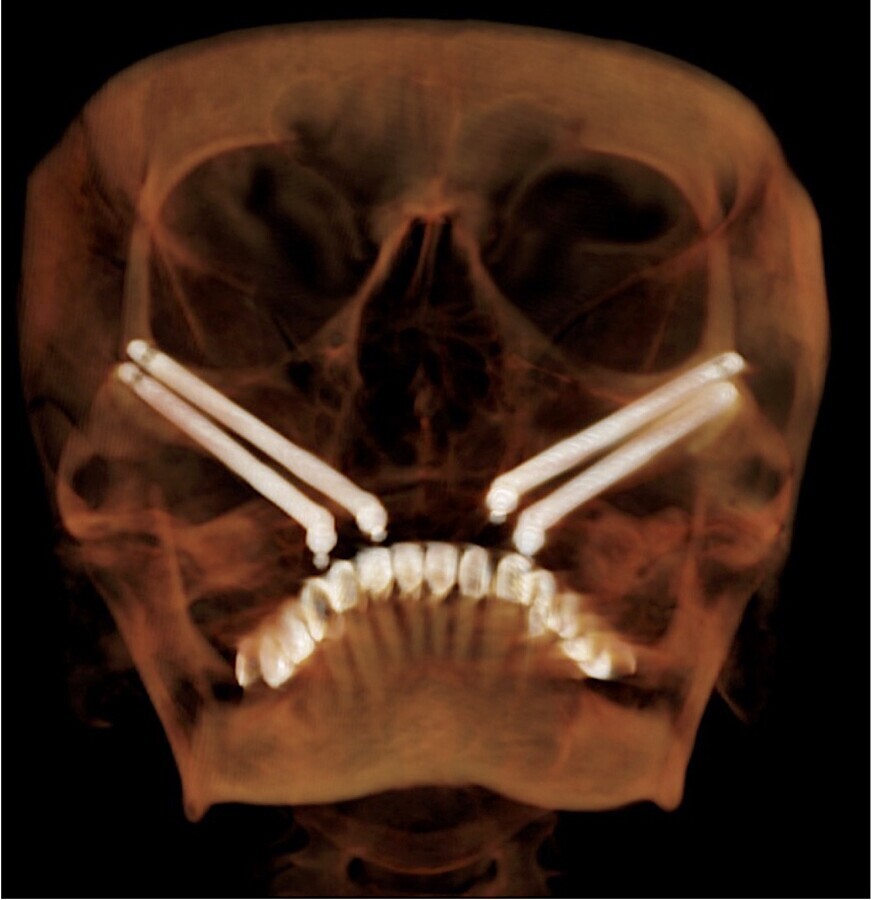

Fig. 2. Planeamiento tridimensional de la colocación de los 4 implantes zigomáticos.

Fig. 8. Imagen topográfica postoperatoria inmediata de Quad Zygoma.